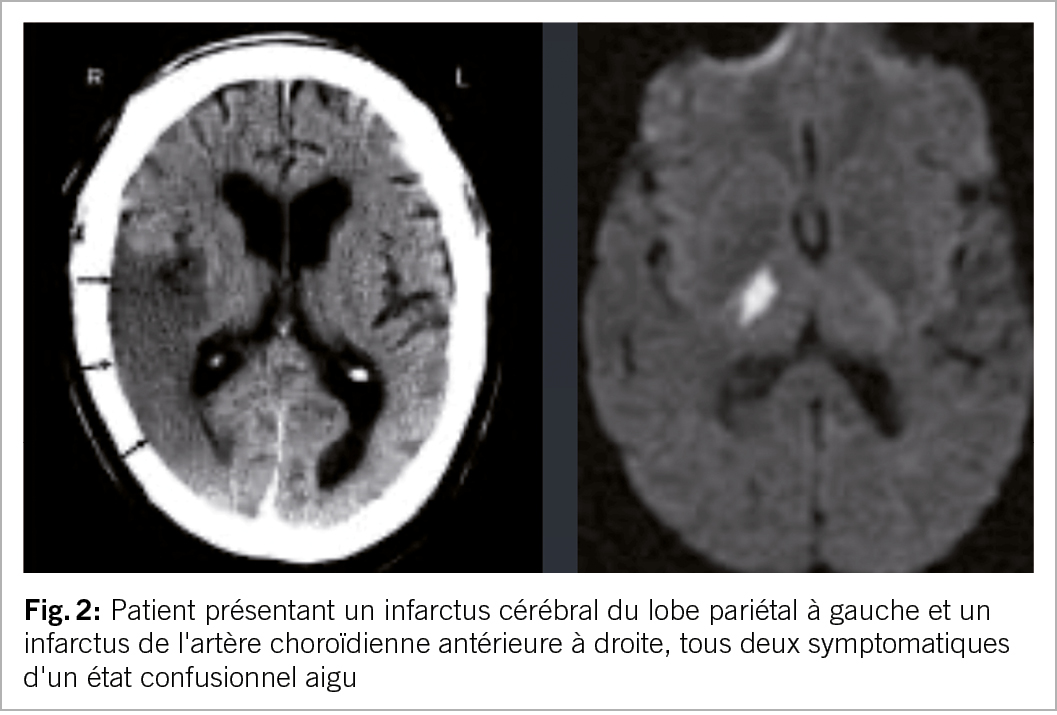

Confusion aiguë

Les AVC peuvent s’accompagner de confusion, d’ excitation ou d’ agitation et être pris à tort pour un délire. Les infarctus du lobe pariétal ou ceux au niveau du territoire de l’artère choroïdienne antérieure sont typiques et peuvent provoquer une confusion aiguë. Un indice clinique utile est l’ apparition soudaine de la confusion (phase très aiguë) chez un patient auparavant asymptomatique (fig. 2).